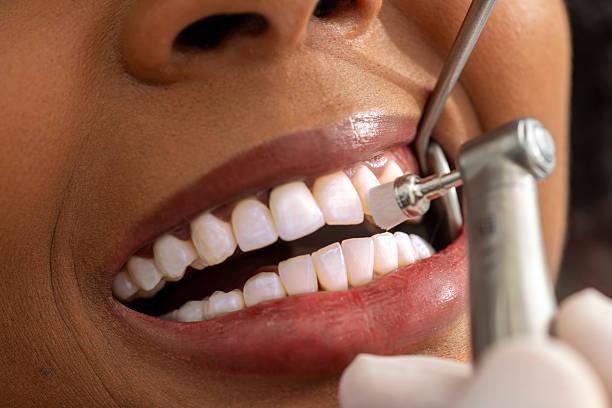

Muitas gestantes se preocupam ao precisar realizar um raio-X odontológico. No entanto, é crucial entender quando este procedimento realmente se faz necessário. O raio-X pode ser indispensável para diagnosticar problemas dentários que não são visíveis a olho nu, como cáries entre os dentes, problemas na estrutura óssea ou mesmo doenças periodontais. Durante a gravidez, essas condições precisam ser monitoradas de perto, já que infecções na cavidade oral podem impactar negativamente a saúde geral da gestante.

Os raios-X utilizam radiação ionizante, que em exposição excessiva, pode ser prejudicial. Felizmente, as doses de radiação usadas nos exames odontológicos são extremamente baixas. Contudo, mesmo pequenas doses podem levantar preocupações entre as gestantes, pois há um potencial risco de afetar o crescimento celular do bebê.

É importante ressaltar que os avanços tecnológicos na área odontológica têm contribuído para minimizar os riscos. Equipamentos modernos emitem níveis muito baixos de radiação. Além disso, os profissionais brasileiros são capacitados e seguem normas de segurança rigorosas para proteger a gestante e o desenvolvimento do feto.

Cuidados Antes de Fazer um Raio-X

Se o raio-X for inevitável durante a gravidez, alguns cuidados podem ser tomados para assegurar a saúde do bebê e da mãe. Primeiramente, é essencial comunicar ao dentista sobre a gravidez, para que medidas de proteção adequadas sejam adotadas. O uso de aventais de chumbo é uma prática comum e importante. Eles protegem o abdômen e a região pélvica da radiação.